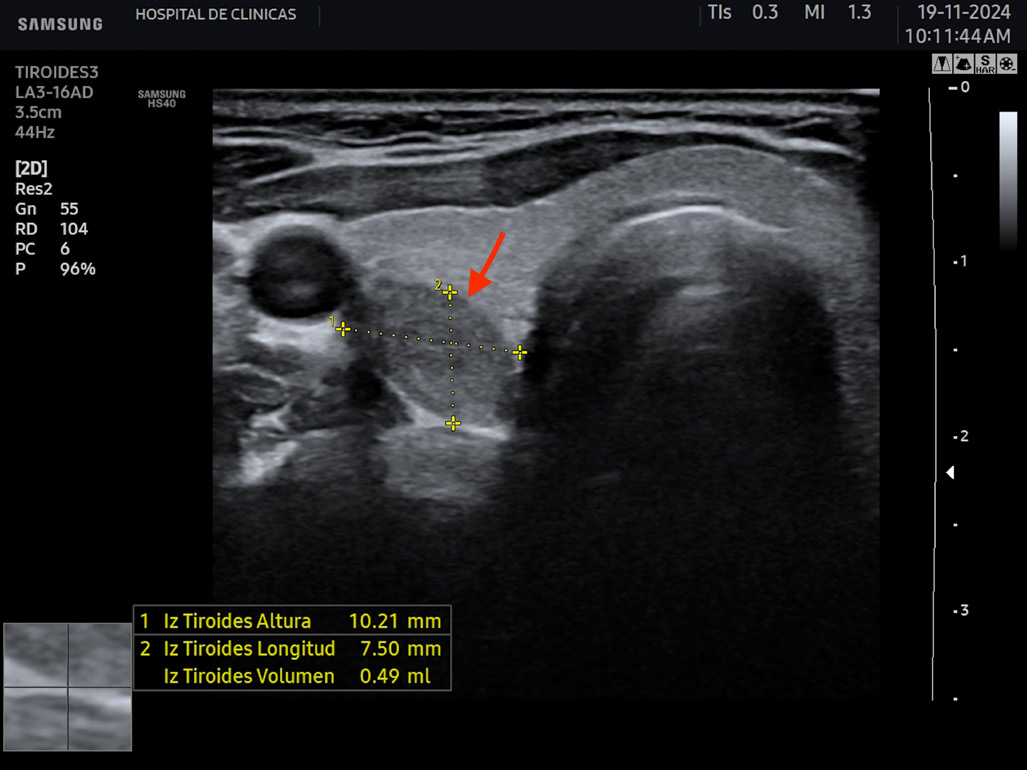

La eco estructura es homogénea, los márgenes son regulares y presenta una cápsula ecogénica, su vascularización es escasa. El rango de referencia para una tiroides normal es de entre cinco y diez vasos visibles dentro de la exploración de cada lóbulo valorado con Doppler color2. Se ha descripto que hasta un 50% de los individuos presentan lóbulo piramidal (Figura 3a y 3b). Este sector, en general, es similar en ecogenicidad, homogeneidad y vascularización al istmo y los lóbulos. En la superficie posterior de los lóbulos tiroideos, especialmente en el segmento inferior, puede visualizarse el tubérculo de Zuckerkandl, un ejemplo de este se puede observar en la figura 4a y 4b. Este es un tabique hiperecogénico fibroso que a menudo genera sombra posterior. Se forma por la extensión del tejido tiroideo de las áreas laterales de los lóbulos hacia el sector posterior, y a menudo exhibe una disminución de la ecogenicidad detrás del mismo. Este proceso puede imitar una lesión tiroidea o paratiroidea y causar dificultades en la interpretación2.